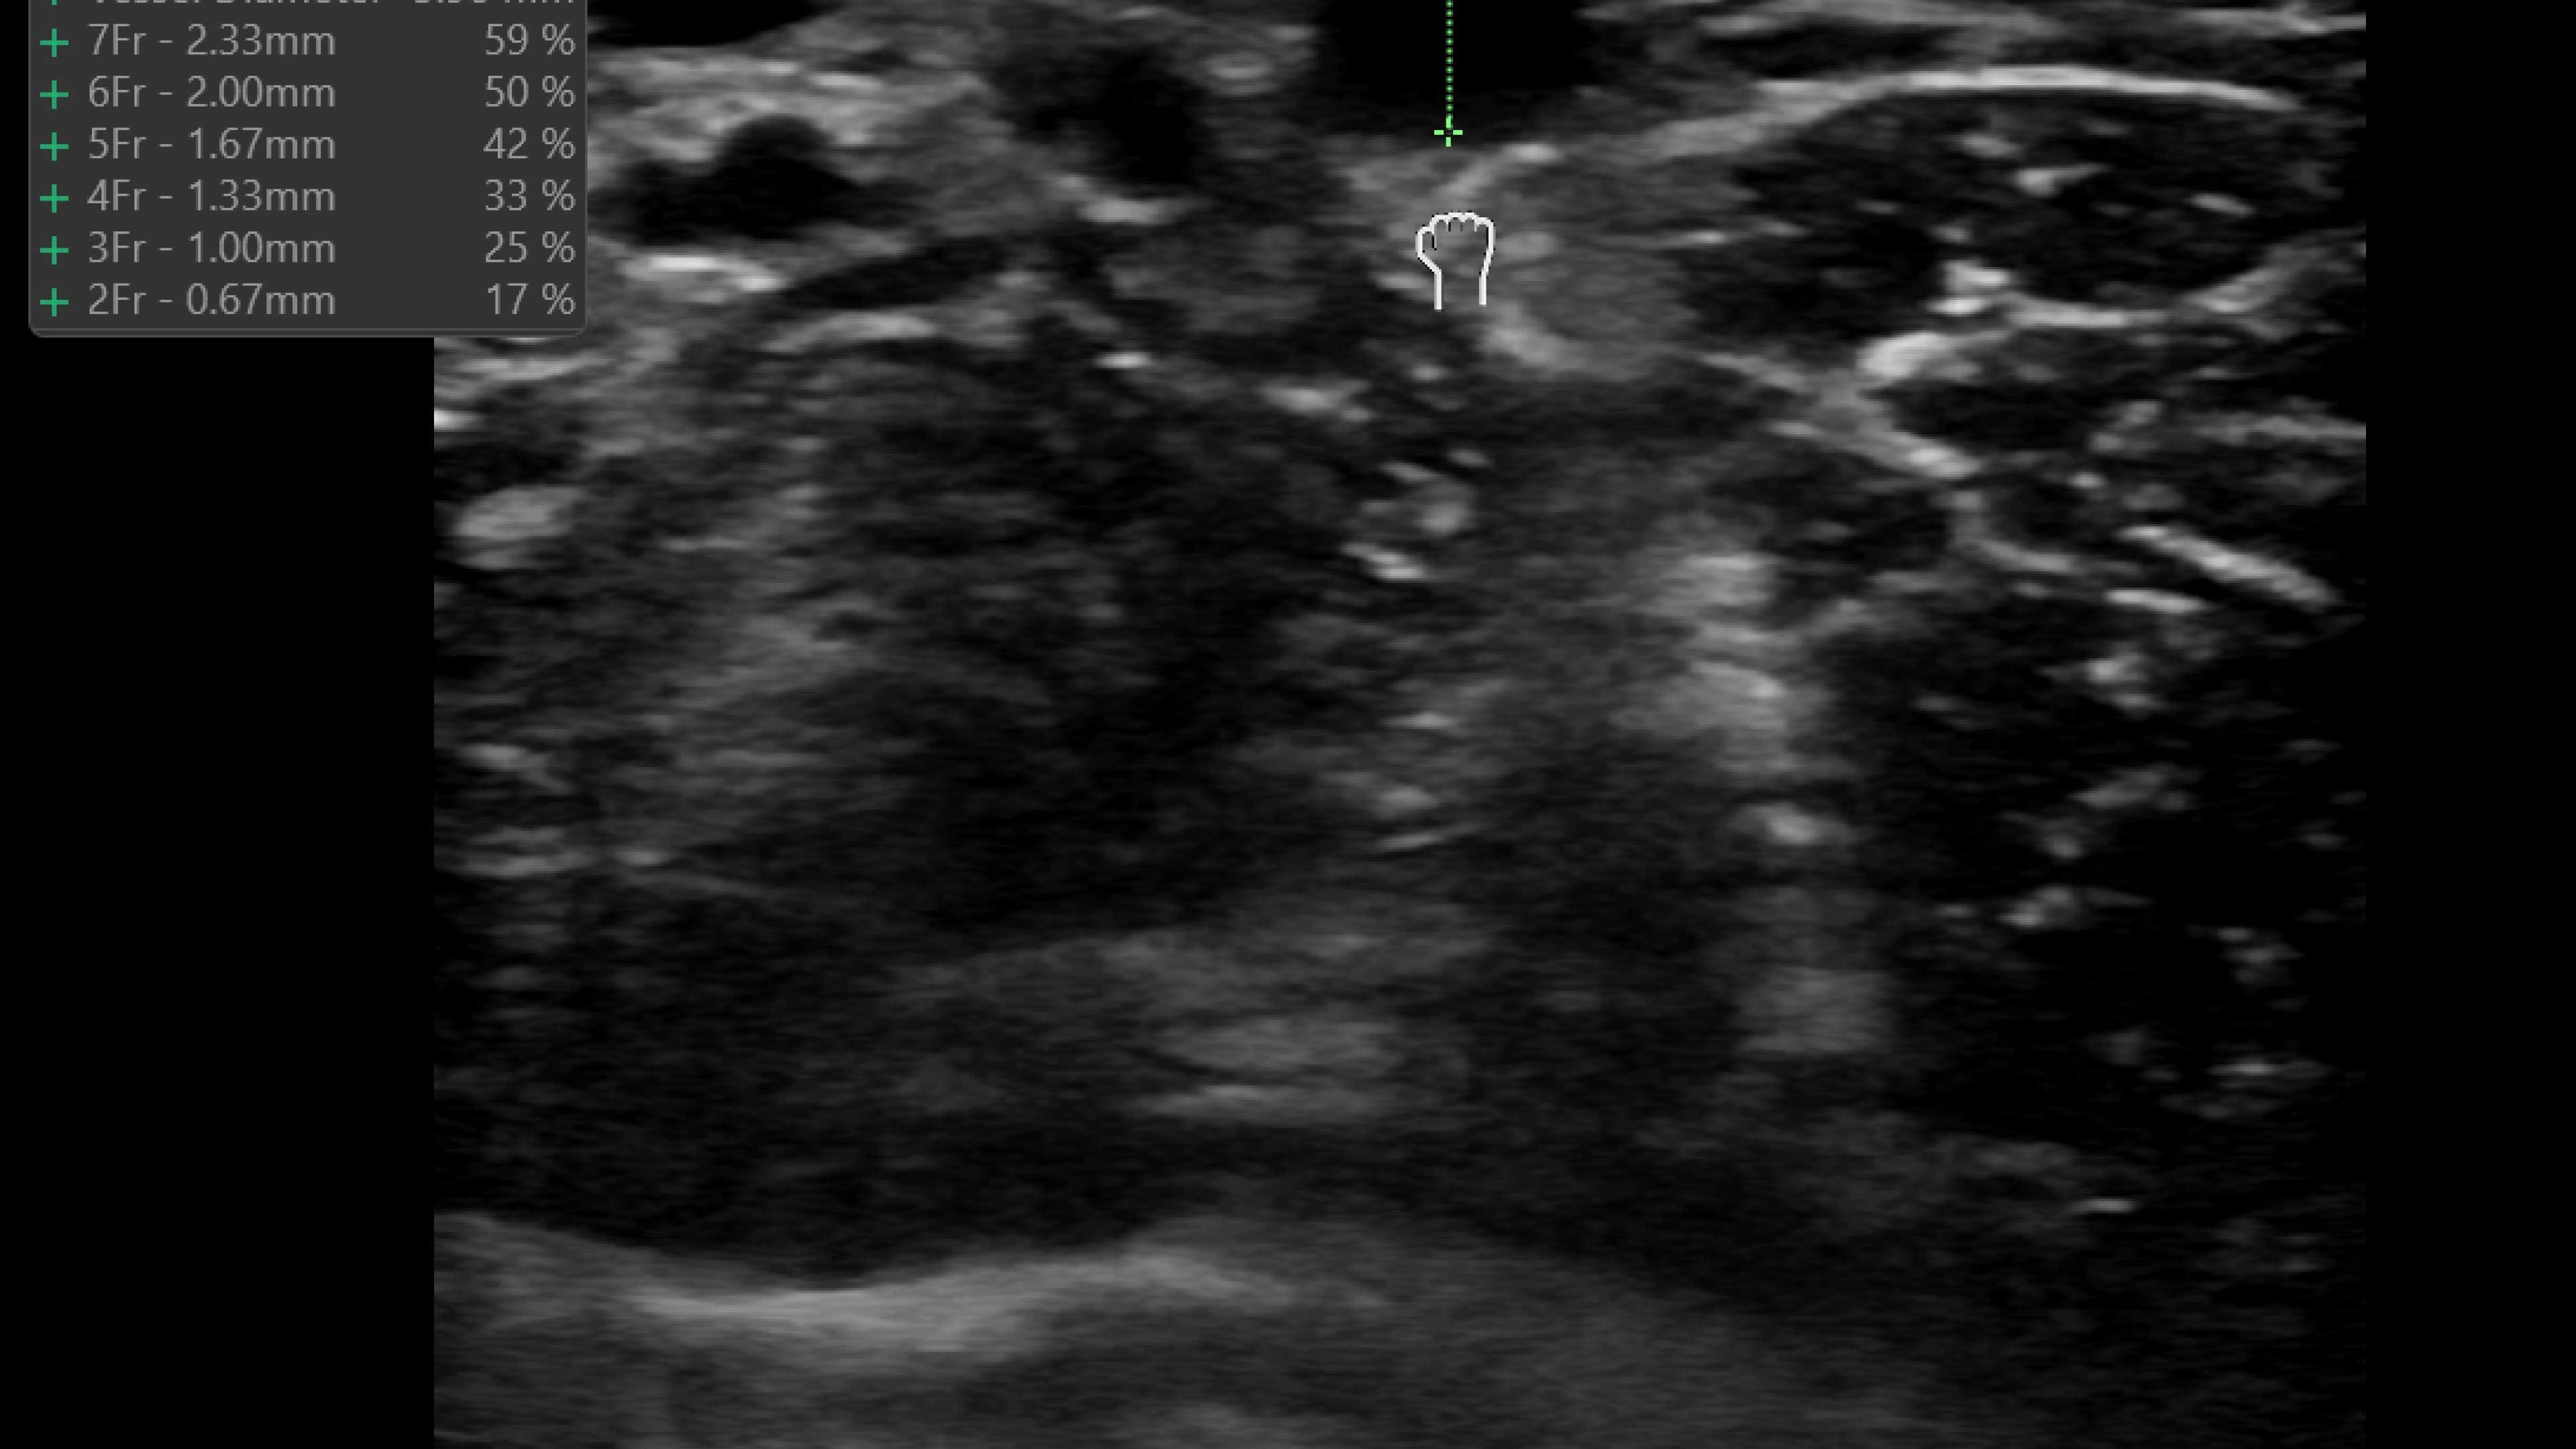

Wireless probe integration

Sync up and go - without wires you’re not tethered to a system or a space

Small yet powerful

Flexible, wireless dual-probes deliver clear images and Venue family software